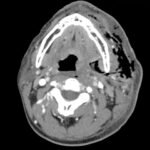

Necrotizing soft tissue infections with mediastinal extension are exceedingly rare. This submission provides dynamic and static visual stimuli (CT images) and a case report describing the history of present illness, initial ED presentation and inpatient course of a 33-year-old man who developed facial necrotizing fasciitis complicated by mediastinitis secondary to odontogenic infection following wisdom tooth extraction. Discussion of the key features of this rare presentation, the diagnostic and therapeutic approaches to making the diagnosis (including CT), and the role of the Emergency Physician, are highlighted.